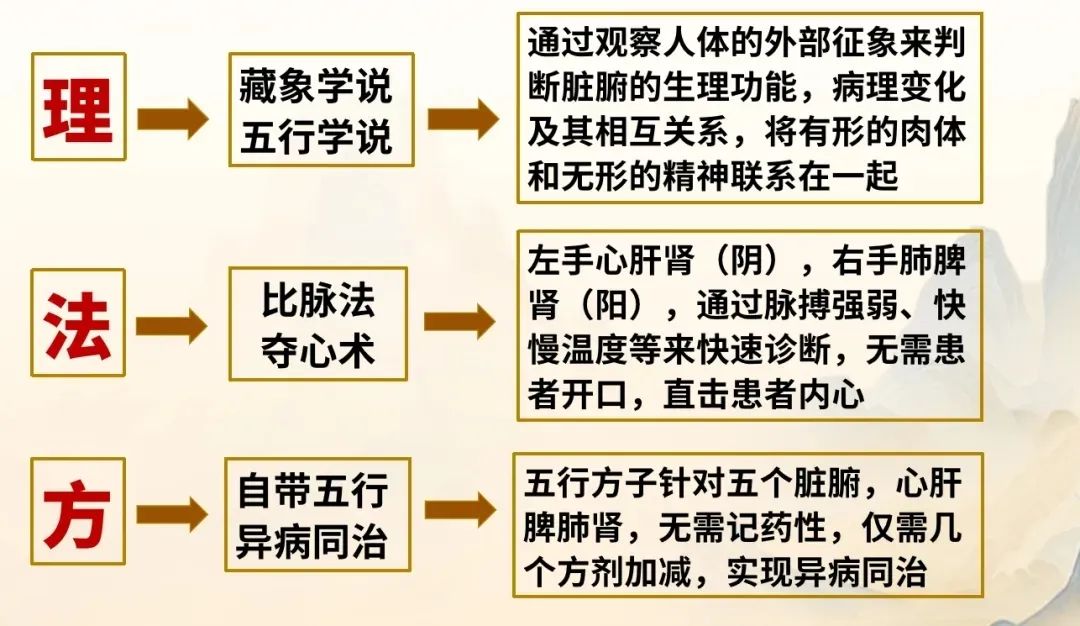

张震从医三十余年,将中医学习的三大高山:理、法、方,全面梳理、逐一击破。

理论基础:《藏象学说》+《五行学说》

张震通过观察人体的外部征象来判断脏腑的生理功能、病理变化及其相互间的关系。

将有形的肉体和无形的精神联系在一起,从而快速、精准辨别病因。

诊断方法:比脉法+夺心术

双手诊脉,主打快准!

比脉法:通过脉搏强弱、快慢温度等快速诊断,不说话知其病证。

夺心术:无需患者开口,知其不可说之事,断其根本病因,直击患者内心!

五行药方:自带五行+异病同治

五行方子针对五个脏腑,心肝脾肺肾,无需记药性,仅需几个方剂加减:

摆脱降压药的束缚、*、妇科病、高血糖、甲状腺结节心脑血管疾病、男科病、鼻炎、寻麻疹等等。

张氏脉法以“夺心”为主旨,融合"诊脉-夺心-开方"三位一体,为更多患者解除病痛。